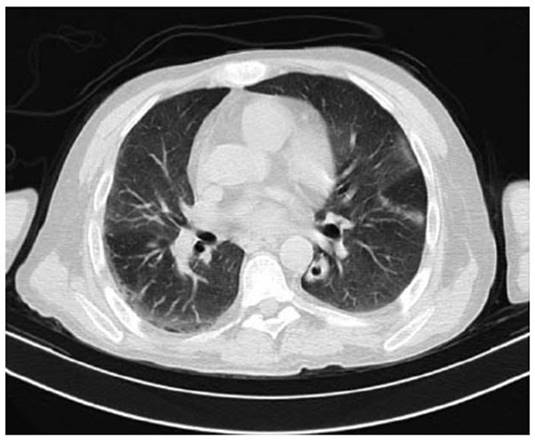

A las 36 horas se evidencia requerimiento de oxigeno con Fio2 32 % con reporte de gases arteriales con trastorno moderado de oxigenación (PaFI 193) con acidosis respiratoria compensada con lactato 2,5 sin signos de dificultad respiratoria y en el momento con mejoría de encefalopatía; Se decide toma tomografía de tórax con hallazgos de opacidades en vidrio esmerilado multilobares de predominio periférico y un nódulo cavitado en el lóbulo inferior izquierdo (Figura 2). Fue llevado a fibro- broncoscopia y lavado bronco alveolar con resultado en estudio citológico con leucocitos aumentados, tinciones negativas y galactomanano negativo (Tabla 2).

Figura 2: Tomografía axial computarizada de alta resolución que evidencia opacidades en vidrio esmerilado en lóbulos superior e inferior izquierdo y lóbulo inferior derecho de predominio periférico y evidencia de un nódulo cavitado en el segmento superior del lóbulo inferior izquierdo.